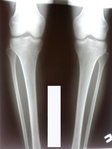

Исходник - 22 года. Павлодар.

Дата операции - 19.06.2018г.

Ротация справа.

Дата снятия аппаратов - 15.10.2018г.

Срок лечения - 115 дней.